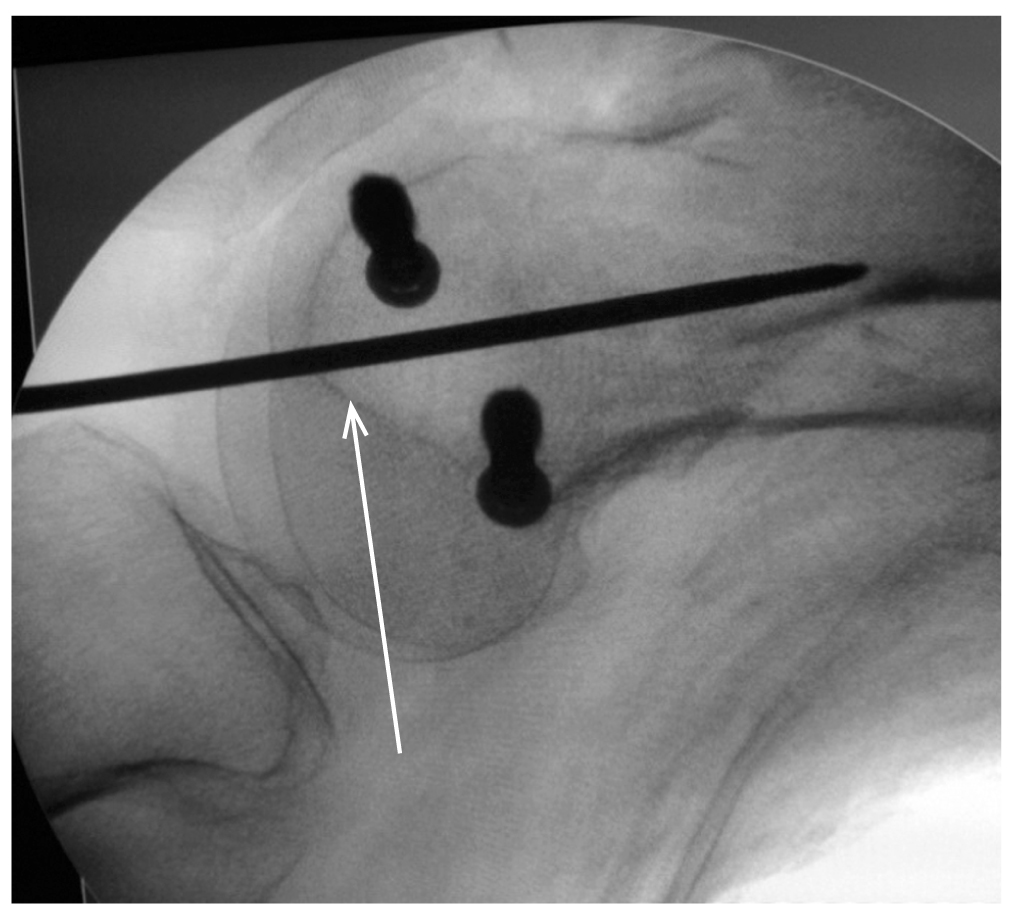

Первым этапом выполняли фиксацию перелома мыщелков стягивающими винтами спереди и сзади от предполагаемой траектории введения штифта после предварительной их репозиции с интраоперационным использованием тазовых щипцов (рис. 4). Из малоинвазивного разреза (до 3 см) сбоку от собственной связки надколенника осуществляли доступ в коленный сустав для проведения направляющей спицы (рис. 5). Затем определяли точку в межмыщелковой ямке, анатомическую ось и траекторию (так называемый угол атаки) для введения ретроградного штифта. Чтобы избежать ятрогенного повреждения крестообразных связок, сначала проводили спицу, ориентируясь на боковом рентгеновском снимке, полученном с помощью электронно-оптического преобразователя, верхнего края линии Blumensaat, а затем выполняли заведение штифта по данной направляющей спице. Все этапы выполнялись под контролем электронно-оптического преобразователя (рис. 6). При правильном введении штифта происходит «саморепозиция» отломков в анатомически правильном отношении, без варусной или вальгусной деформации ДОБК. При необходимости для этого используют поляризующие винты. Дальнейшая хирургическая техника описана в клинических примерах.

Рис. 6. Точка введения направляющей спицы (стрелка) в боковой проекции над линией Blumensaat. / Fig. 6. The point of the guiding wire entry in the lateral view superior to the Blumensaat line.